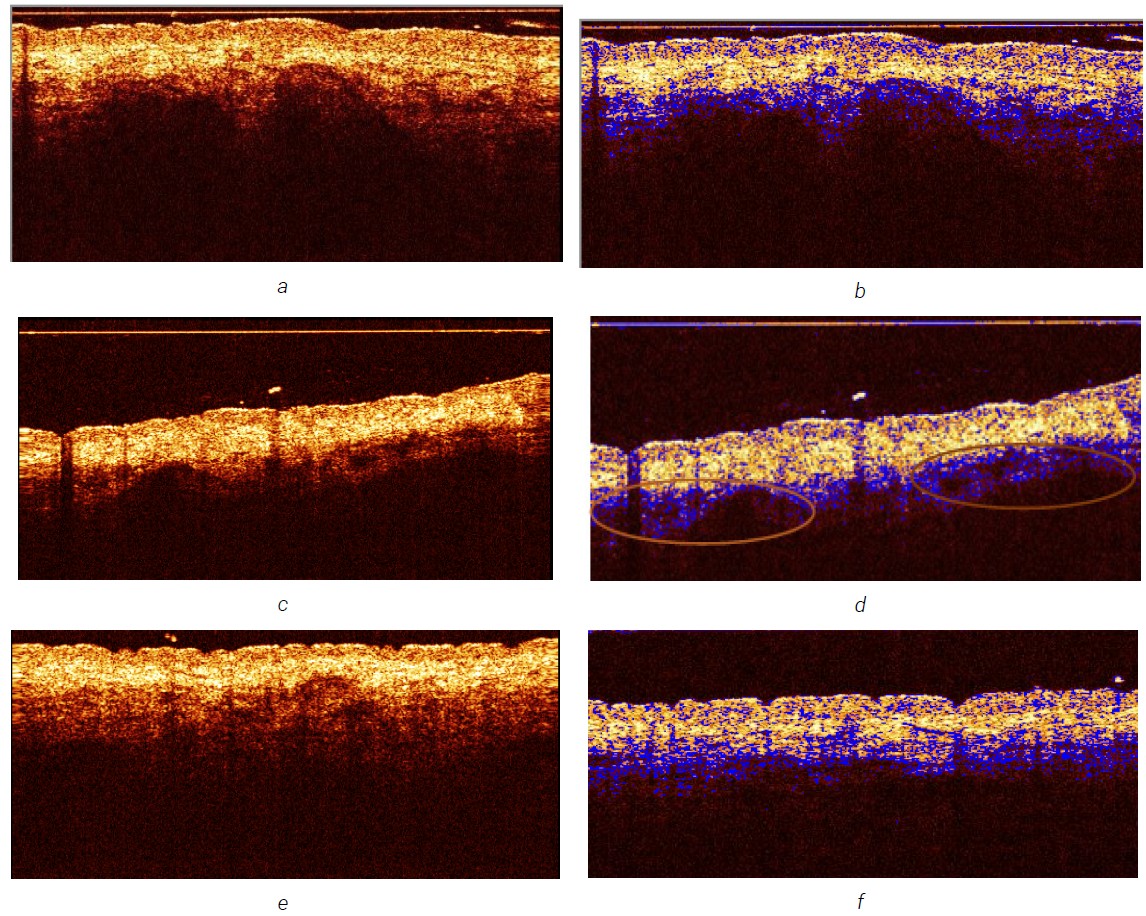

The images of healthy skin of various anatomical locations showed a typical five-layer structure of skin images without pathological inclusions (Figure 4).

The same changes in varying degrees of severity were observed in the images of all foci of mastocytosis, regardless of the location and age of the patient. Within the optical equivalents of the lower part of the epidermis, the papillary layer of the dermis and, in some cases, the reticular layer of the dermis, round, oval and elongated dark zones of low signal intensity were clearly defined. The zones were of different sizes, with relatively clear boundaries (Figure 5), and corresponded to the histological description of mastocyte clusters (Figure 6) in shape, size (from 100 microns and more), characteristics and location (marked with red circles).

When identifying clusters of mast cells, these zones were differentiated from skin vessels, also represented by zones of low signal intensity. According to the available data, the resolution of this modification of the OCT device allows for the detection of pathologically dilated vessels within the papillary layer of the dermis only in patients with pathology of the main vessels (varicose veins, malformations) [11]. There were no such pathologies in the examined patients.

Fig. 5. OCT images of the skin of the lateral part of the trunk of a patient with mastocytosis in the area of a wheal (Darier’s sign +) (a) and inflammatory macule (c), non-inflammatory macule (e) and OCT images of similar areas processed by the Lumen Stratis software (b, d, f)

In addition, it has been previously shown that vessels in OCT images of vertical skin sections are represented by slit-shaped, oval and tree-shaped areas of low signal with clear boundaries, without a contour in the case of visualization of venules or with a light contour in the case of visualization of arterioles [11]. When analyzing OCT images of pathomorphological elements in patients with mastocytosis, the absence of clear boundaries was noted in areas of low intensity, defined as clusters of mast cells (Figure 5).

Thus, the OCT images within the epidermis and upper dermis visualized the desired clusters of mast cells. Attempts to visualize these objects using high-frequency ultrasound were unsuccessful. This was primarily due to the low resolution of the method, as well as the lack of the ability to clearly and in detail visualize the epidermis and dermo-epidermal junction zones of most interest to us, which are practically inseparable from the “sensor-gel-skin” interface in high-frequency ultrasound images.

Non-inflammatory macules | Yellow-brown coloration, pigment pseudonetwork (Figure 6a, b) | Rounded and elongated dark zones of low signal intensity of various sizes with relatively clear boundaries (Figure 5e, f) | The epidermis of normal thickness with hyperpigmentation of basal keratinocytes without pigment loss, infiltrates in the reticular dermis (Figure 6c) |

Inflammatory macules, papules | Peripheral erythema, punctate vessels, pigment pseudonetwork (Figu-‑re 3b, c) | The above signs in combination with optical signs of edema (decrease in signal intensity and increase in the height of the optical layers) within the optical equivalents of the epidermis and dermis (Figure 5c, d) | Superficial perivascular mast cell infiltrates in the papillary and reticular dermis (Figure 7) |

Wheals (Darier’s sign) | Erythema and linear dilated vessels (Figure 3c), intense redness with barely discernible pigment pseudonetwork (Figure 3d) | Pronounced optical signs of edema in the form of a decrease in signal intensity within all visualized layers, an increase in the depth of the useful signal, a decrease in the clarity of the boundaries, an increase in the visualization of the optical equivalents of vessels within the reticular layer of the dermis (Figure 5a, b) | The dermis is somewhat edematous, the vascular pattern is enhanced, the endothelium is swollen, the vascular lumens are dilated, there are scattered perivascular infiltrates of mast cells, fibroblasts, histiocytes and eosinophils (Figure 8a, b) |

In the clinical diagnosis of mMPCM, the most difficult are non-inflammatory spots, which are caused by mast cell infiltrates, histologically determined in the reticular dermis. On OCT images, they can look like apparently healthy skin (Figure 5e). Dermoscopy at the onset can observe a pale yellow-brown coloration with a gradual formation of a pigment pseudonetwork, which is associated with hyperpigmentation of the basal layer of the epidermis (Figure 6).

When the infiltrates are located in the papillary dermis, both macules and papules can be observed in patients (Figure 7). Dermoscopic examination demonstrates a bright yellow-brown staining of the lesion with a peripheral vascular pattern (Figure 3b, c). OCT visualizes a bright pattern of vascular reaction to mast cell infiltration of the papillary dermis (Figure 5c, d).